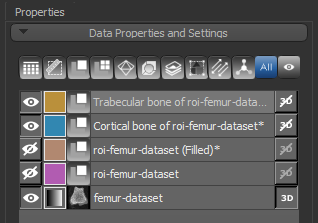

At the end of the process, a new region of interest (Filled) will appear in the Data Properties and Settings panel.

- Click Next to continue to the next segmentation step.

Segmentation of the cortical and trabecular bone is the most critical step for the accurate quantification of selected morphometric indices. Two methods — Kohler and Buie — are available for segmenting cortical and trabecular bone. The input of the automated segmentation is a bone segmentation in which bone mineralization is present (see Performing Initial Bone Segmentations) and a filled region of interest in which the bone segmentation are filled. The output of the process is two regions of interest listed below:

At the end of the process, two new regions of interest — Cortical bone and Trabecular bone — appear in the Data Properties and Settings panel.